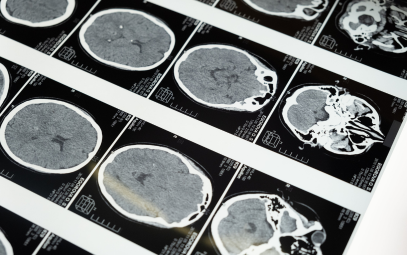

A 66-year-old woman presented with sudden-onset headache and a brief loss of consciousness. CT head revealed diffuse aneurysmal subarachnoid hemorrhage (aSAH) with intraventricular hemorrhage. Vascular imaging confirmed a ruptured left anterior communicating artery aneurysm and several unruptured blister aneurysms. On arrival, she was lethargic but arousable and able to follow commands (Hunt and Hess grade III). A bedside external ventricular drain (EVD) was placed for cerebrospinal fluid diversion and intracranial pressure (ICP) monitoring, followed by craniotomy and aneurysm clipping the same day.

In light of this, neurosurgery elected to replace the EVD. The new catheter produced normal ICP values and improved waveform fidelity, confirming the prior device’s malfunction. There was a partially obstructing clot in the removed EVD catheter. CT scans were done in addition to TCD ICP calculation. Prior to the EVD being replaced, the CT showed slight worsening of hydrocephalus with an EVD tract hemorrhage and deep placement of the EVD. CT obtained after EVD replacement showed some improvement of the hydrocephalus. Immediately after EVD replacement, opening pressure was normal (8 mmHg) which was congruent with the calculated ICPs from TCD. It is likely that deep placement and clot found within EVD catheter caused falsely elevated ICP readings.